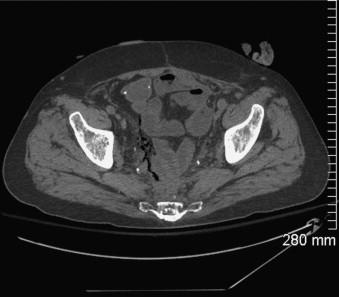

We present an 81 year old male who developed a rectovesicular fistula following radiation for metastatic prostate cancer. He had recurrent bleeding and infections and underwent a pelvic exenteration which was complicated by a persistent pelvic abscess requiring placement of a transperineal drainage catheter. After months of persistent drainage, he noted decreased output and irrigated the catheter with 3% hydrogen peroxide. He presented to the emergency room with fever, diarrhea and abdominal cramping but no rebound or guarding. CT depicted free air in the pre-sacral space extending into the retroperitoneum and diffusely throughout the peritoneum. Given his clinical exam and upon review of imaging, we assumed his radiographic findings were related to the direct instillation of hydrogen peroxide into his chronic pelvic cavity.

Instillation of hydrogen peroxide into a chronic pelvic cavity resulted in a benign pneumoperitoneum. This effect of hydrogen peroxide is a significant and potentially treatment altering radiographic finding.